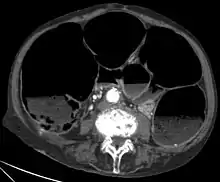

CT-Scan showing a Cross-section of the abdomen of an elderly lady with an IPO.

CT-Scan showing a Cross-section of the abdomen of an elderly lady with an IPO. - CT scans